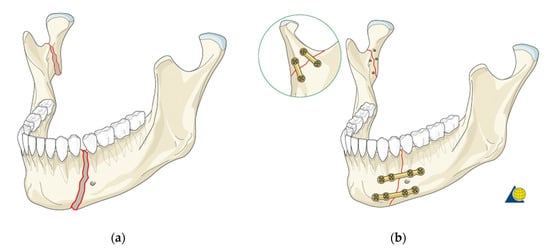

- Creation of an accurate model of the mandible together with the temporomandibular joint. The main assumption was to create a model that could be used for numerical analyses of various clinical cases, allowing the simulation of the work of fixing elements, assessment of the strength and durability of the fixation, and at the same time, without unnecessary simplifications, reflect real human anatomy. The input data were DICOM images obtained from medical imaging using computed tomography. Obtaining three-dimensional models of individual anatomical structures required the segmentation of tomographic images and then edition of the generated surface objects. Reverse engineering software for free modeling and a CAD program for parametric modeling were used.

- Taking into account the current achievements and shortcomings of the existing models of the mandible, it was necessary to investigate the effect of simplifications of the temporomandibular joint. Various degrees of simplification of the mandible model were designed, which made it possible to check various configurations of the FEM analysis assumptions and to select the variant that best reflects real conditions. The most important criterion for simplifications was a sufficient reflection of the system biomechanics. This required the creation of a force action scheme based on the actual impact of muscles on the mandible and the introduction of boundary conditions to simulate the appropriate load state. As a result of the performed calculations, maps of stresses in the mandible were obtained, and their analysis allowed to assess the influence of the studied simplifications.